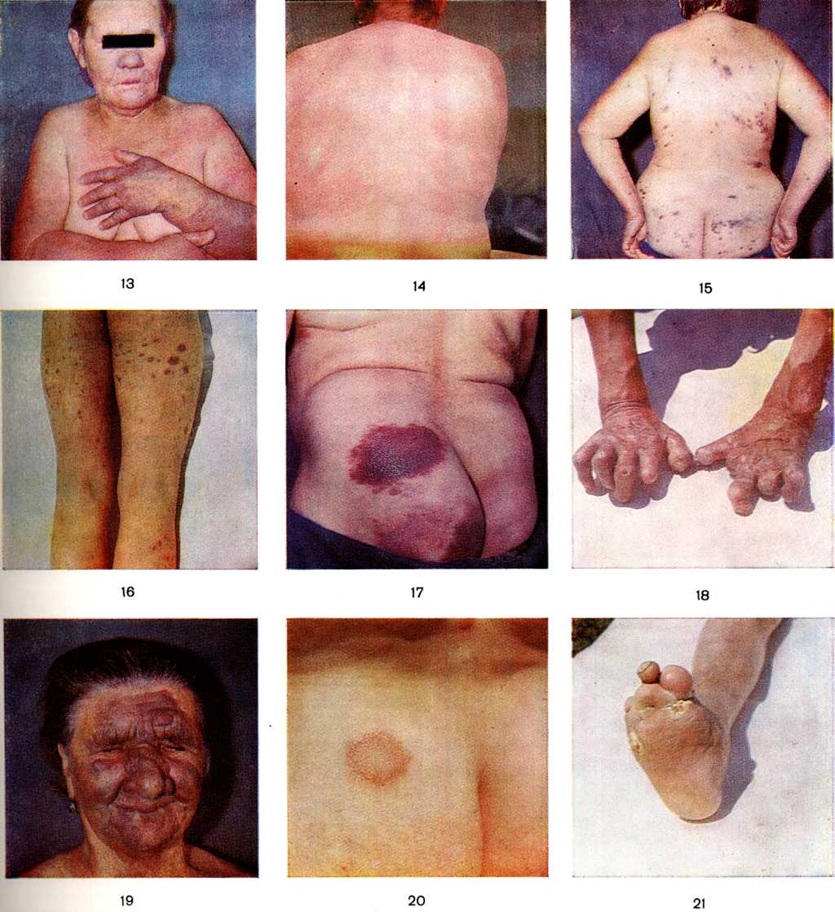

ЛепраЛепра [греческий lepra; синонимы: болезнь Гансена, гансениаз, ганзеноз; устаревшие названия: проказа, elephantiasis graecorum, lepra arabum, lepra orientalis, финикийская болезнь, satyriasis, leontiasis, скорбная болезнь, скорбь, северная болезнь (якуты), крымская болезнь, крымка, чёрная немочь, лисья короста, ленивая смерть, болезнь Святого Лазаря и другие] — хроническая генерализованная инфекционная болезнь человека, вызываемая микобактериями лепры, характеризующаяся поражением кожи, слизистых оболочек, периферической нервной системы, внутренних органов. Оглавление Статистика и географическое распространение Физическая и социальная реабилитация ИсторияЛепра относится к числу древнейших из известных заболеваний человека. Существует мнение, что Лепра входила в группу кожных болезней, описанных в книгах «Rigveda Samhita» и «Sushrutas Ayurvedas» (Индия, 1500 — 1000 лет до нашей эры) под общим названием «kushtha», в папирусе Эберса и Бругша (Египет, 13 00—1000 лет до нашей эры) — под названием «uchedu» и в библии — под названием «zaraath» (проказа). Сравнительно полные описания кожных и неврологический проявлений Лепра встречаются в литературе Индии и Китая, относящейся к 8—5 веков до нашей эры Описания в индийской книге «Sushruta Samhita» (6 век до н. э.) и в китайской книге «Nei Ching Su Wen» (5 век до нашей эры) узлов, изъязвлений, выпадения бровей, мутиляций, поражений глаз, изменений носа, нарушений чувствительности, деформации конечностей и параличей свидетельствуют об умении диагностировать поздние типичные проявления Лепра. К этому же периоду относится разработка профилактических наставлений против распространения Лепра, включая расторжение брака. В европейских странах Лепра впервые встречается в 5—3 веков до нашей эры, прежде всего в Греции и Италии, куда она была занесена из Египта, Финикии и стран Азии в результате развития торговых связей, войн и других передвижений народов. Распространению Лепра в Европе способствовал массивный занос её в 1 век до н. э. римскими солдатами Помпея, возвращавшимися из длительных походов в страны Юго-Восточной Азии. В Южную и Центральную Америку Лепра была занесена европейцами в 16 —18 веков. В первых упоминаниях о Лепра европейских авторов (Аристотель, 4 век до нашей эры) болезнь называлась satyriasis или leontia (leontiasis). Наиболее полно клинические, симптомы заболевания описаны в Европе во 2 век врачами Аретеем (Агеtaios) и особенно Галеном, который выделял шесть основных признаков Лепра: воспаление кожи, язвы, утолщение нижних конечностей, львиное лицо, выпадение волос и мутиляции. В Европе болезнь длительное время фигурировала под названием «elephantiasis». Только в 3 век христианский богослов Ориген (около 185—254 годы) указал на то, что название «elephantiasis» соответствует библейскому названию «zaraath», а поскольку 70 толковников, переводившие библию в 3 век до нашей эры на греческий язык, перевели термин «zaraath» словом «lepra», болезнь следует называть «лепра». |

Возбудитель Лепра человека был описан в 1874 год норвежским врачом Г. Гансеном. Он выявил его в соскобе с поверхности разреза узла у больного узловатой Лепра. В 1879 год нем. микробиолог А. Нейссер предложил методы окраски бактерий Лепра Именно поэтому в литературе иногда возбудитель Лепра описывается как микобактерия Гансена — Нейссера. В 1882 год была установлена кислото и спирто-устойчивость возбудителя Лепра. В первые годы после открытия возбудителя Лепра его называли Bacillus leprae, Coccothrix leprae, Streptothrix leprae, дифтероид, затем он был включён как самостоятельный вид в род Mycobacterium Lehmann et Neumann, 1896. Окончательно принадлежность возбудителя Лепра к микобактериям (смотри полный свод знаний) была доказана после обнаружения Дрейпером (P. Draper, 1976) в его составе типичной миколевой кислоты, а также работами по изучению его антигенного состава. Наиболее правильными видовыми названиями возбудителя Лепра являются Mycobacterium leprae, Mycobacterium leprae hominis, Mycobacterium Hanseni. В соответствии с классификацией Берджи род Mycobacterium входит в семейство Mycobacteriaceae, порядок Actinomycetales, класс Schizomycetes.

Возбудитель Лепра, как правило, имеет вид прямой или слегка изогнутой палочки с закруглёнными концами. Размеры микобактерии варьируют: длина от 1,0 до 4,0 — 7,0 микрометров, диаметром 0,2—0,5 микрометров. В лепромах встречаются также зернистые, кокковидные, нитевидные, ветвистые, булавовидные, почкующиеся, гантелевидные формы возбудителя. Как и другие микобактерии, микобактерии Лепра грамположительны, окрашиваются по Цилю — Нельсену в красный цвет; в клетках тканей они выявляются в виде шаровидных плотных скоплений (глоби), в которых отдельные бактерии располагаются параллельно друг другу, что нередко сравнивают с видом сигарет в пачках («сигарные пачки»).

Электронно-микроскопическими исследованиями установлено, что ультраструктура возбудителя Лепра принципиально не отличается от строения других видов грамположительных бактерий. На поверхности микобактерий Лепра выявляется равномерный электроннопроницаемый (осмиофобный) слой толщиной 5—10 нанометров (наружный диффузный слой клеточной стенки). За ним следует осмиофильный слой клеточной стенки толщиной от 3 до 10 нанометров, состоящий из двух очень тонких некоторое, плотно прилегающих друг к другу. Непосредственно к внутренней поверхности клеточной стенки примыкает наружный слой цитоплазматической мембраны (рисунок 1), представляющей собой, как и у других бактерий, трёхслойную мембрану толщиной 7,5—9 нанометров. В бактериальной клетке встречаются 1—2 мезосомы с выраженным полиморфизмом (петлеобразные, везикулярные, трубчатые, пластинчатые, гроздевидные). В цитоплазме выявляется сравнительно небольшое количество рибосом, сферические электронно-плотные включения волютина диаметром 20—50 нанометров, включения, имеющие вид ограниченных мембраной вакуолей (предположительно липоиды), и гомогенные тельца, природа которых остаётся неизвестной. Ядро не имеет определённой формы, расположено в центре клетки вдоль её длинной оси, не ограничено мембраной. Иногда в лизирующихся под воздействием химиотерапии клетках микобактерий Лепра выявляются спороподобные образования (рисунок 2 и 3).

|

|  |

Рис. 1. | ||

|

|  |

Рис. 2. | ||

|

|  |

Рис. 3. | ||

|

|  |

Рис. 4. | ||

Основным способом размножения микобактерий Лепра является деление материнской клетки и врастания поперечной перегородки. Микобактерия Лепра является облигатным внутриклеточным паразитом тканевых макрофагов или клеток ретикулоэндотелиальной системы, проявляет выраженный тропизм к коже и периферическим нервам, но на поздних стадиях развития процесса встречается также во многих других клетках и тканях организма. В тканевой клетке микобактерии Лепра размножаются только в цитоплазме (рисунок 4); внутриядерный паразитизм для них нехарактерен. Микобактерии в лепрозных клетках иногда отграничены от цитоплазмы клетки-хозяина фагосомной мембраной. На поздних стадиях инфекции паразитирование возбудителей Лепра человека сопровождается нарушением строения эндоплазматического ретикулума и митохондрий клетки-хозяина.

Патологическая анатомия

Гистологический исследование биопсийного материала имеет важное значение для установления диагноза и прогноза болезни. Биопсии подвергаются участки поражённой кожи, изредка — поверхностно расположенные нервы. Морфологически изменения при Лепра проявляются в виде гранулем двух полярных типов — лепроматозного (LL) и туберкулоидного (ТТ), а также трёх групп — погранично-туберкулоидной (ВТ), пограничной (ВВ) и погранично-лепроматозной (BL).

Гистологически лепроматозный тип характеризуется лепроматозной гранулемой кожи, которая представляет инфильтрат, расположенный в сетчатом слое, отделённый от эпидермиса непоражённой зоной коллагеновой ткани. Основными клеточными элементами лепроматозной гранулемы являются лепрозные клетки; кроме того, наблюдаются отдельные плазматические, лимфоидные клетки, единичные фибробласты, многоядерные пенистые клетки (цветной рисунок 1—6). Лепрозные клетки относятся к макрофагам, характеризуются бледным ядром и «пенистой» цитоплазмой (рисунок 5) за счёт содержания липидов. Лепрозный макрофаг на ранних стадиях содержит жирные кислоты, фосфолипиды, ненасыщенные липиды; на стадии развития процесса преобладают нейтральные жиры и кислотные липиды. Большинство исследователей считает, что основная масса липидов представляет собой продукт метаболизма и распада микобактерий Лепра. Наиболее характерная особенность лепрозного макрофага — нахождение и размножение в нем большого количества микобактерий Лепра, то есть явление незавершённого фагоцитоза (смотри полный свод знаний). В цитоплазме лепрозной клетки выявляется высокий уровень окислительно-восстановительных ферментов, кислой фосфатазы, неспецифической эстеразы и не обнаруживается активность липазы. Для гистологический картины LL характерно также наличие капилляров со значительным сужением их просвета за счёт пролиферации и набухания эндотелиальных клеток, содержащих большое количество микобактерий типа «глоби». Кожные нервы пронизаны инфильтратами из микробосодержащих клеток (цветной рисунок 7 и 10). Микобактерии обнаруживаются также в клетках эндоневрия. В лепроматозных поражениях большой давности отмечается частичное или полное разрушение придатков кожи (фолликулов волос, сальных и потовых желёз).

|

|  |

Рис. 5. | ||

|

|  |

Рис. 7. | ||

|

|  |

Рис. 8. | ||

Клиническая картина

Туберкулоидный тип (ТТ) отличается более лёгким по сравнению с лепроматозным типом (LL) течением, лучше поддаётся лечению. Поражаются кожа и периферические нервы, реже некоторые внутренние органы. Микобактерии Лепра выявляются при гистологический исследовании очагов поражения, а в соскобах кожных поражений и слизистой оболочки носа отсутствуют. Лепроминовая проба положительная.

Кожные проявления в зависимости от стадии развития болезни имеют вид одиночных пятен или папулёзных высыпаний, бляшек, бордюрных или саркоидных элементов. Пятна при ранней ТТ гипопигментные или слегка эритематозные, с чётко очерченными краями. В дальнейшем по краю пятен появляются мелкие полигональные красноватосинюшные плоские папулы, они быстро сливаются в сплошные несколько возвышающиеся над уровнем кожи воспалительные бляшки, трансформирующиеся затем в бордюрные элементы. Поверхность бляшек гладкая, иногда шелушится. Наиболее типичным, классическим проявлением развитой ТТ является большая эритематозная бляшка с резко очерченным валикообразно приподнятым краем и склонностью к периферическому росту. По мере увеличения бляшки центральная её часть уплощается с появлением атрофии и гипопигментации. Это приводит к появлению больших кольцевидных сливающихся бордюрных элементов — фигурный туберкулоид (цветной рисунок 20). Ширина бордюра может колебаться от нескольких миллиметров до 2— 3 сантиметров и более. Наружный край его приподнят, внутренний — уплощён. Размеры бляшек и бордюрных элементов могут быть от 10— 15 миллиметров до обширных очагов, захватывающих большую часть спины, груди, поясницы. Расположение высыпаний обычно асимметричное, на любом участке тела.

Одной из разновидностей поражения кожи при этой форме Лепра являются саркоидные (люпоидные) образования размером от 2—3 миллиметров до 2—3 сантиметров красно-бурого цвета с чёткими границами и гладкой поверхностью, склонные к группированию, локализующиеся обычно на лице и конечностях, реже на туловище. При регрессе всех элементов на их месте остаются гипопигментные пятна или участки атрофии кожи (смотри полный свод знаний).

Поражение периферической нервной системы и обусловленные этим сенсорные, трофические и вазомоторные нарушения выявляются очень рано. В очагах поражения отмечается расстройство температурной, болевой и тактильной чувствительности (смотри полный свод знаний), выпадение пушковых волос, изменение пигментации, нарушение салоотделения, потоотделения (смотри полный свод знаний), сухость кожи, иногда гиперкератоз (смотри полный свод знаний). Зона расстройства температурной и болевой чувствительности выходит на 0,5—1,5 сантиметров за видимые границы высыпаний, а нарушение тактильной чувствительности и потоотделения регистрируется только в пределах высыпных элементов. На ранней стадии нередко отмечается диссоциация нарушений чувствительности, в отдельных случаях возможно кратковременное повышение всех видов чувствительности (гиперестезия), за которым непременно следует вначале снижение чувствительности, а затем полная анестезия (смотри полный свод знаний). В дистальных отделах конечностей могут быть нарушены все виды чувствительности. Вокруг бляшек и пятен можно обнаружить утолщённую поверхностную веточку кожного нерва, чего не бывает при LL. Поражение нервных стволов выражается в диффузном или чёткообразном их утолщении, болезненности, а иногда в развитии колликвационного некроза в местах, наиболее уязвимых для микобактерий Лепра (участки предилекции). Обычно вначале поражается нервный ствол, в зоне иннервации которого располагаются бляшки. Без лечения поражение нервов развивается по типу полиневрита (смотри полный свод знаний). В результате поражения крупных стволов периферической нервной системы развиваются парезы и параличи, трофические язвы, контрактуры пальцев, атрофия мелких мышц, изменения ногтей, мутиляции и другие изменения кистей и стоп (цветной 18 и 21). Часто встречается поражение лицевого нерва, что сопровождается лагофтальмом (смотри полный свод знаний) и парезом мышц лица (маскообразное лицо). Другие черепные нервы в процесс вовлекаются редко. В запущенных случаях могут нарушаться рефлексы с пяточных (ахилловых) сухожилий и сухожилия трёхглавой мышцы. Проприоцептивная чувствительность, как правило, не страдает.

Лепроматозный тип (LL) отличается большим разнообразием клинические, проявлений на коже (нечёткие пятна, инфильтраты, бляшки, узлы), ранним вовлечением в процесс слизистых оболочек, внутренних органов и более поздним — нервной системы, труднее поддаётся лечению. Во всех высыпаниях выявляются громадные количества микобактерий Лепра Лепроминовая реакция отрицательная.

Высыпания на коже чаще представлены многочисленными эритематозными или эритематозно-пигментными пятнами, характерными признаками которых являются симметричное расположение, небольшие размеры и отсутствие чётких контуров. Наиболее часто пятна локализуются на лице, разгибательных поверхностях кистей, предплечий и голеней, а также на ягодицах. Поверхность их гладкая, блестящая. Со временем первоначальный красный цвет пятен приобретает бурый или желтоватый (медный, ржавый) оттенок. Чувствительность и потоотделение в пределах пятен не нарушены. В течение длительного времени (месяцы, годы) пятна остаются без изменений, иногда исчезают, но чаще трансформируются в инфильтраты или лепромы (цветной рисунок 15 и 16). При развитии инфильтрата пятна приобретают вид ограниченных бляшек или значительных участков поверхностной инфильтрации кожи без чётких границ, постепенно переходящих во внешне неизменённую кожу. Развитие пареза сосудов и гемосидероза обусловливает бурый или синюшно-бурый цвет инфильтрата (цветной рисунок 13 и 14). Инфильтрация кожи сопровождается усилением функции сальных желёз, в результате чего кожа в местах поражений становится жирной, блестящей, лоснящейся. Расширение фолликулов пушковых волос и выводных протоков потовых желёз придаёт коже вид апельсиновой корки. Потоотделение в области инфильтратов сначала снижается, а в поздних стадиях — полностью прекращается. На ранних стадиях процесса рост пушковых волос не нарушается, в более позднем периоде (3—5 и более лет) наблюдается выпадение бровей (начиная с наружных сторон) и ресниц, а также пушковых волос на участках инфильтрации кожи, возможно выпадение волос бороды, усов. При диффузной инфильтрации кожи лица естественные морщины и складки углубляются, надбровные дуги резко выступают, нос утолщён, щеки, губы и подбородок имеют дольчатый вид — «львиная морда» (facies leonina, (цветной рисунок 19). Волосистая часть головы, внутренние части век, подмышечные ямки, локтевые сгибы и подколенные ямки, как правило, не поражаются (иммунные зоны), но при распространённом процессе в этих зонах выявляются гистопатологические изменения, характерные для LL. В области инфильтратов часто уже на ранних стадиях появляются одиночные или множественные бугорки и узлы (лепромы), размеры которых варьируют от 1 — 2 миллиметров до 2—3 сантиметров Лепромы чаще локализуются на лице (надбровные дуги, лоб, крылья носа, подбородок, щеки), мочках ушных раковин, а также на кистях, предплечьях, голенях, реже — на бёдрах, ягодицах, спине. Они резко отграничены от окружающей кожи, безболезненны, в скарификатах с них при микроскопическом исследовании обнаруживаются микобактерии Лепра (цветной рисунок 12).

Лепромы могут быть дермальными или гиподермальными. Гиподерма л ьные лепромы вначале выявляются пальпаторно, но в дальнейшем они достигают дермы и становятся видимыми. Дермальные лепромы вначале имеют вид овальных папул, постепенно превращаясь в бугорки красновато-ржавого цвета, возвышающиеся в виде полушарий над уровнем кожи. Поверхность их гладкая, лоснится, часто испещрена телеангиэктазиями, иногда шелушится. Из плотновато-эластических они становятся более мягкими, а в редких случаях фиброзного перерождения — очень плотными. Иногда они подвергаются рассасыванию, оставляя после себя пигментированное, несколько запавшее пятно. Наиболее частым исходом лепромы при отсутствии лечения является изъязвление. Процесс развивается вяло, торпидно, без выраженных воспалительных явлений и заканчивается образованием небольшого гипопигментного рубца. Реже наблюдается быстрый распад лепром, начинающийся с поверхности или центра узла, с образованием неглубоких, длительно не заживающих язв, которые могут сливаться, образуя обширные язвенные поверхности. Края язв крутые или подрытые, инфильтрированные, несколько возвышаются над окружающей кожей, могут быть болезненными, впоследствии становятся омозоленными. Дно язв покрыто серовато-жёлтым. налётом. После заживления остаётся ровный, слегка запавший, гипохромический, иногда келоидный рубец. Во всех случаях поражаются слизистые оболочки носа, а в запущенных случаях — слизистые оболочки полости рта, гортани, а также спинка языка и красная кайма губ. Ринит, носовые кровотечения нередко отмечаются ещё до появления кожных поражений. Слизистая оболочка носа гиперемирована, отёчна, с небольшими эрозиями; в дальнейшем появляются лепромы, инфильтрация, массивные корки, резко затрудняющие носовое дыхание. Распад лепром, расположенных на хряще перегородки носа, приводит к её перфорации и деформации носа. В запущенных случаях возможно изъязвление лепром на слизистой оболочке мягкого неба. Поражение области голосовых складок может привести к резкому сужению голосовой щели, афонии.

Специфические поражения органа зрения до лечения сульфоновыми препаратами встречались примерно у 80% больных Лепра При LL поражаются передний отдел глазного яблока и веки, чаще всего встречаются эписклериты (смотри полный свод знаний Склерит), очаговый кератит (смотри полный свод знаний Кератит), иридоциклиты (смотри полный свод знаний Иридоциклит), помутнение хрусталика, а также конъюнктивиты и блефариты. Развитие эписклеритов начинается с появления у лимба роговицы гиперемии, на месте которой образуется диффузный инфильтрат или небольшая (диаметром 2—4 миллиметров) лепрома. В нелеченых случаях эписклеральные лепромы увеличиваются, могут прорастать в радужку и ресничное тело. Кератиты характеризуются появлением мелких белых (просовидных) лепром на фоне очагового помутнения роговицы. В дальнейшем лепромы увеличиваются, изъязвляются, в роговой оболочке появляются сосуды (лепрозный паннус), кератит становится диффузным, распространяется на всю роговицу. В запущенных случаях возможно поражение радужки (гипертрофия пигментного зрачкового ободка, распад пигмента, явления ирита с перикорнеальной инъекцией сосудов, светобоязнью, болями). Появление мелких лепром и отложения фибринозного экссудата в виде белых хлопьев и нитей на поверхности радужки приводят к деформации зрачка и нарушению аккомодации. В прошлом хронический иридоциклиты являлись основной причиной слепоты больных Лепра На веках могут локализоваться диффузные инфильтраты и лепромы, что приводит к выпадению ресниц. Особенностью лепрозного конъюнктивита является отсутствие отделяемого и слабовыраженные явления раздражения.

При LL специфический процесс часто поражает периферическую нервную систему, лимфатических, узлы, печень, стенки большинства кровеносных сосудов, яички. Бедренные, паховые, поднижнечелюстные, подмышечные и другие лимфатических, узлы (кроме грудных и брыжеечных) увеличены, плотной консистенции.

Поражение периферической нервной системы проявляется сравнительно поздно и развивается, как правило, по типу симметричного полиневрита. Нарушения чувствительности в зоне кожных высыпаний долгое время отсутствуют, но со временем они всегда проявляются. Осевые цилиндры нервов сравнительно устойчивы к развитию в них лепрозного инфильтрата, чем объясняется довольно длительное сохранение его функции. Однако в дальнейшем наблюдается инфильтрация лепрозными клетками всего поперечника нервного ствола, по мере развития которой теряется чувствительность до полной анестезии. Поражённые нервные стволы утолщены, плотные, гладкие. На очень поздних стадиях неврита, кроме расстройств чувствительности, развиваются различные трофические и двигательные нарушения (лагофтальм, парез жевательной и мимической мускулатуры, амиотрофии, контрактуры, мутиляции, прободающие и трофические язвы стоп). Глубокие виды чувствительности, а также сухожильные и надкостничные рефлексы обычно сохраняются без нарушений.

Хронический гепатиты выявляются довольно рано, они имеют склонность к обострениям, особенно в период реактивных фаз. Печень может быть увеличена, иногда болезненна, отмечаются различные нечётко выраженные функциональный нарушения (смотри полный свод знаний Гепатит), обусловленные наличием мелких просовидных лепром в парапортальных областях и дольках печени.

Орхит (смотри полный свод знаний) и орхоэпидидимит характеризуются хронический течением с последующим нарушением функции яичек (инфантилизм и гинекомастия). Иногда при распространённой LL наблюдаются нарушения менструального цикла.

При LL, как и при других формах Лепра, наблюдаются изменения ногтей, они становятся тусклыми, сероватыми, утолщёнными, изрезанными продольными бороздками, ломкими, легко отслаиваются, крошатся.

Стёртые и атипичные формы лепроматозного типа. К первым относятся одиночные пятна, инфильтраты и лепромы (абортивное течение), а также очень мелкие лепромы, развившиеся вокруг фолликулов пушковых волос (фолликулярные лепромы). Из атипичных проявлений описаны ихтиозиформные, склеродермоформные, пеллагроидные, эризипелоидные, лихеноидные, герпетиформные, псориазиформные высыпания, гистоидная Лепра и лепра Лусио.

Гистоидная Лепра клинически характеризуется особой чёткостью границ и обрывистыми краями элементов (бляшек и узлов), на которых нередко бывает шелушение, точечные вдавления в центре.

Лепра Лусио (синонимы: лепра Лусио — Альварадо, диффузная LL, диффузная лепра Лусио—Латапи, пятнистая диффузная лепра) впервые описана в Мексике Лусио и Альварадо (R. Lucio, I. Alvarado) в 1852 год и подробно изучена Латапи (F. Latapi, 1938). Это распространяющаяся на всю поверхность тела диффузная LL без отдельных пятен, бляшек и лепром. Кожа становится блестящей и напряжённой, как при склеродермии. Волосяной покров иногда отсутствует. Диффузная инфильтрация лица (лунообразное лицо), хриплый голос, Отёки ног напоминают микседему. Лепра Лусио характеризуется слабо выраженной воспалительной реакцией и Васкулитом, сопровождающимся тромбозом кожных кровеносных сосудов, что приводит к обширным изъязвлениям кожи. Васкулит, встречающийся при других формах Лепра, обычно не сопровождается тромбозом. Лепра Лусио, сопровождаемая обширными изъязвлениями, называется лепрой Святого Лазаря. На поздних стадиях лепры Лусио развивается ихтиоз.

Встречается также так называемый сливная пятнистая LL, при которой едва заметные гипопигментированные или эритематозные пятна, быстро сливаясь, образуют единое пятно, покрывающее всю кожу, за исключением иммунных зон. При этих разновидностях Лепра решающим в диагностике заболевания является бактериоскопическое исследование скарификатов поражений кожи: при LL в них всегда обнаруживается большое количество микобактерий Лепра

Пограничные группы. В клинике других групп лепры (ВТ, ВВ, BL) в той или иной мере выражены признаки обоих полярных типов (пограничные состояния).

Погранично туберкулоидная группа (ВТ). Кожные высыпания при ВТ по внешнему виду, расположению и состоянию чувствительности очень напоминают проявления ТТ. Но при этом пятна и бляшки обычно меньших размеров, множественные, встречаются элементы с нечёткими границами (цветной таблица, ст. 80, рисунок 17). Как правило, имеются утолщения периферических Нервных стволов, нарушения чувствительности, потоотделения и роста пушковых волос, но по сравнению с ТТ все эти проявления менее выражены. Реакция на лепромин слабоположительная или положительная.

Пограничная лепра (ВВ). Кожные проявления, помимо сходства с основными группами, характеризуются типичными, не присущими полярным типам признаками: наряду с многочисленными асимметричными эритематозными пятнами, часто неправильной формы, с нечёткими границами или бляшками с отчётливым пологим краем и более выпуклой центральной частью, как правило, имеются «пробитые», или «штампованные», пятна и бляшки, получившие название дырочек сыра. Это обусловлено появлением в центральной части высыпаний чётко очерченных участков регресса (стихания) с гипопигментированной или нормальной по цвету кожей. При бляшках кожа в участках регресса уплощается, элемент сначала принимает вид «перевёрнутого блюдца», а затем возвышающихся над уровнем кожи округлых или полосовидных бордюрных элементов с чётким обрывистым внутренним краем (в отличие от бордюрных элементов при ТТ, где внутренний край уплощён). Как правило, такие бордюрные проявления приобретают фиолетовую окраску. Поблизости от пятнистых и бордюрных элементов обычно выявляются гроздья мелких высыпаний — сателлитов. Довольно рано развиваются множественные асимметричные поражения периферических нервных стволов. В самих высыпаниях выявляется умеренное нарушение чувствительности. Потоотделение на высыпаниях обычно не нарушено, пушковые волосы частично сохранены. Лепроминовая проба, как правило, отрицательная, реже слабоположительная.

Погранично лепроматозная группа (BL). Как и при LL, основными элементами BL являются не имеющие отчётливых границ пятна, папулы, бляшки, диффузные инфильтраты и узлы. Основной отличительной особенностью BL является наличие «пробитых», «штампованных» высыпаний и округлых или полосовидных бордюрных элементов с приподнятым внутренним краем. Характерно также наличие небольших вдавлений в центре некоторых папул и бляшек. Высыпания не столь множественны, как при LL, нередко располагаются асимметрично. На некоторых элементах уже в ранней стадии выявляется снижение чувствительности. Функция потовых желёз не страдает, чаще не нарушен и рост пушковых волос. Как и в случае пограничной Лепра, при BL обычно выявляется утолщение периферических нервных стволов, что, в отличие от LL, может предшествовать появлению высыпаний на коже.

Не развиваются такие типичные для LL проявления, как выпадение бровей и ресниц, деформация носа, поражение глаз, изъязвление слизистой оболочки носа, facies leonina. Реакция на лепромин всегда отрицательная. При бактериоскопии во всех кожных высыпаниях в большом количестве выявляются микобактерии Лепра